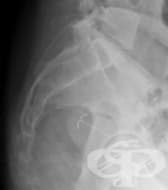

Рентгенографията на дванадесетопръстника представлява образен метод на изследване, при който се прав...